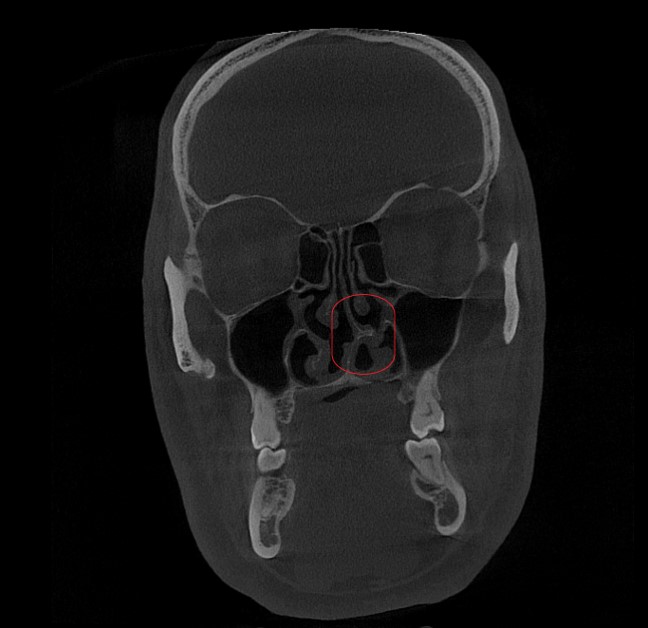

Для уточнения диагноза и оценки состояния околоносовых пазух и структур носа было проведено обязательное обследование, входящее в структуру первичного осмотра:

КТ (компьютерная томография) околоносовых пазух. Подтвердила наличие анатомического затруднения носового дыхания - искривление носовой перегородки и увеличение (гипертрофию) нижних носовых раковин.